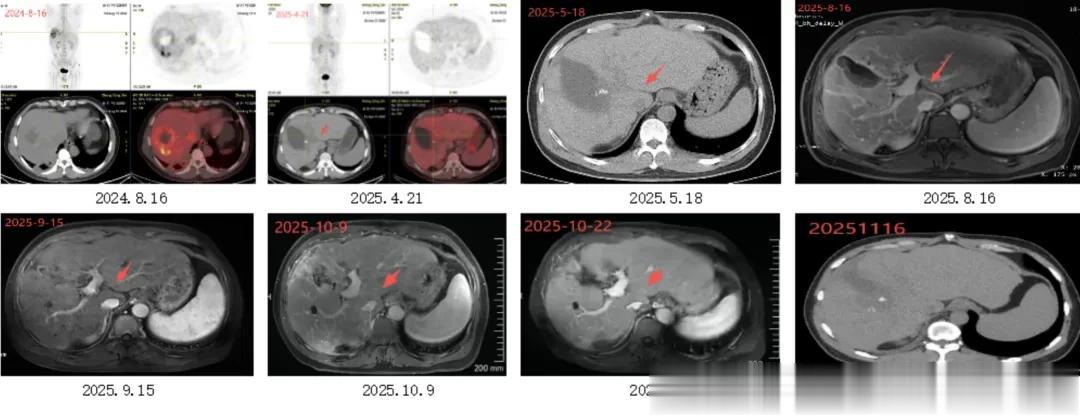

PET-CT显示:肝脏右叶多个低密度团块状,较大的已有93mmx64mm,SUVmax 13.1,考虑肿瘤浸润转移可能性大。

直到2025年4月,PET-CT确认:

① 术区周围多发点状代谢增高灶,大小约13mm×9.3mm;术区边缘见多个实性结节影,大小约12mm× 9mm;

② 左肺上叶结节,大小约12mm×10mm,考虑肿瘤转移可能;

③ 右侧膈上、肝门区、腹膜后区多发淋巴结,较大者位于右侧膈上,大小约30mm×6mm,其中右侧膈上淋巴结考虑肿瘤转移可能,余淋巴结肿瘤转移不能除外。

▶ 肝脏及肝周病变:尾状叶及下腔静脉区域2025年11月PET-CT显示该区域病灶消失,邻近下腔静脉淋巴结未明确显示,提示治疗有效或病灶活性抑制;

影像表现:2025.4.21PET-CT示:肝门区淋巴结肿大;2025.5、2025.8复查同前;2025.9至2025.11复查示:肝门区淋巴结略缩小。